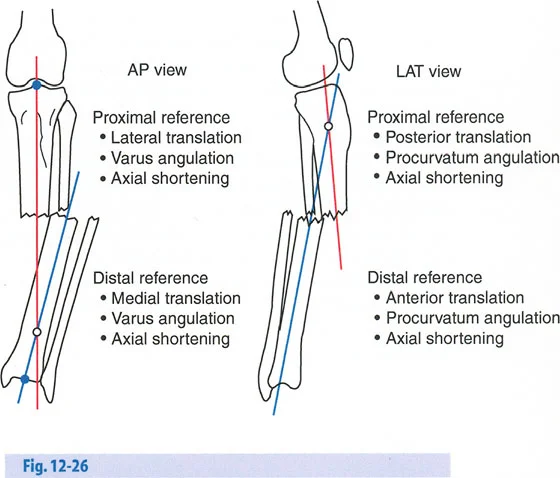

- الأشعة السينية الطويلة للطرفين (Long-leg Standing X-rays): هذه الأشعة ضرورية لتقييم المحور الميكانيكي للطرف بالكامل أثناء الوقوف. تسمح بتحديد مركز دوران الانحراف (CORA) بدقة، وهو النقطة التي يجب أن تتمحور حولها عملية التصحيح.

القياسات الهندسية:

- باستخدام صور الأشعة السينية الطويلة، يقوم الأستاذ الدكتور محمد هطيف بإجراء قياسات هندسية دقيقة لتحديد الزوايا غير الطبيعية (مثل mLDFA و MPTA)، ومقدار القصر، ودرجة الدوران، وأي انحرافات في المحور الميكانيكي. هذه القياسات هي الأساس لتخطيط الجراحة بدقة متناهية.